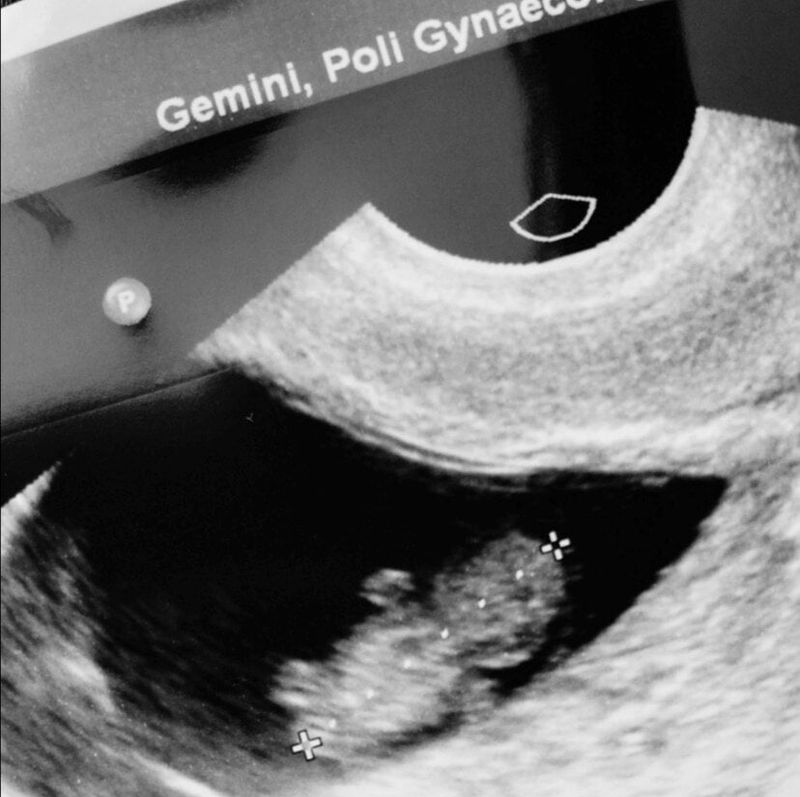

“Kijk liefje, dat is ons babytje”, zeg ik tegen onze 5- jarige dochter die mee was naar de tweede echo. “En zie je dat daar? Dat is het hoofdje! Maar weet je lieverd? Ons babytje is ziek geworden”, zeg ik al kijkend naar een vruchtje zonder hartactiviteit. Voor de zekerheid gooit de verloskundige er nog een gekleurd beeld over heen om te kijken of het hartje echt niets meer doet. Terwijl ik mijn wang aan de binnenkant tot bloedens toe open bijt om niet in huilen uit te barsten, vertel ik haar dat haar broertje of zusje niet meer leeft en niet bij ons thuis komt, maar naar de hemel gaat. “Oh, dan gaat ze naar grote opa toe!”. “Ja lieverd, dan gaat het kindje inderdaad naar grote opa toe”, antwoord ik. En ze accepteerde dat. Gewoon, zomaar en zo flexibel.

Na de ‘diagnose’ volgden er keuzes. Afwachten, opwekken met medicatie of een curretage. Ik besloot het een week af te wachten en te kijken of voetreflextherapie zou helpen. Maar toen de 12 weken grens in zicht kwam, besloot ik toch voor de medicatie, cytotec te gaan. Ik voelde me namelijk nog hartstikke zwanger. Maar hoe zwanger ben je eigenlijk, als het kindje in je buik al twee weken overleden in het vruchtwater ligt? Nee, voor de twaalf weken wilde ik het kwijt zijn. Die magische grens, wanneer het aan iedereen verteld mocht worden, die wilde ik niet voorbij. Want ja, volgens veel mensem stelt het dan pas wat voor. Iemand in onze directe omgeving die het na de eerste echo van 8 weken wist, zei; “Tsja, wij vertellen het eigenlijk ook pas met 12 weken”. Ja, want als ik het na 12 weken had verteld was het kindje minder dood gegaan? Of wacht. Het kindje was evengoed dood gegaan, maar dan had jij niet de kans gehad om deze kutopmerking te maken. En ik kon volgens degene maar blij zijn dat het kindje het niet overleefd had, want dan was er vast iets niet goed geweest. Ik vond het zo enorm frustrerend. Ik zat thuis met een schitterende echo foto. Armpjes, beentjes, hoofdje en een lijfje. Voor mij een perfect kindje en eigenlijk wilde ik laten zien hoe enorm trots ik was op dit kleintje. Want het was wel van ons het was een broertje of zusje van Lotje en Noud. En ik wilde dit delen, en ik wilde ook huilen, vertellen waarom ik verdrietig was. Maar dan heb je het taboe. Want zoiets houd je 12 weken stil, zodat we allemaal kunnen doen alsof dit kindje nooit bestaan heeft, iets wat zo enorm gewenst en geliefd was. Waarom moeten we doen alsof het nooit bestaan heeft?